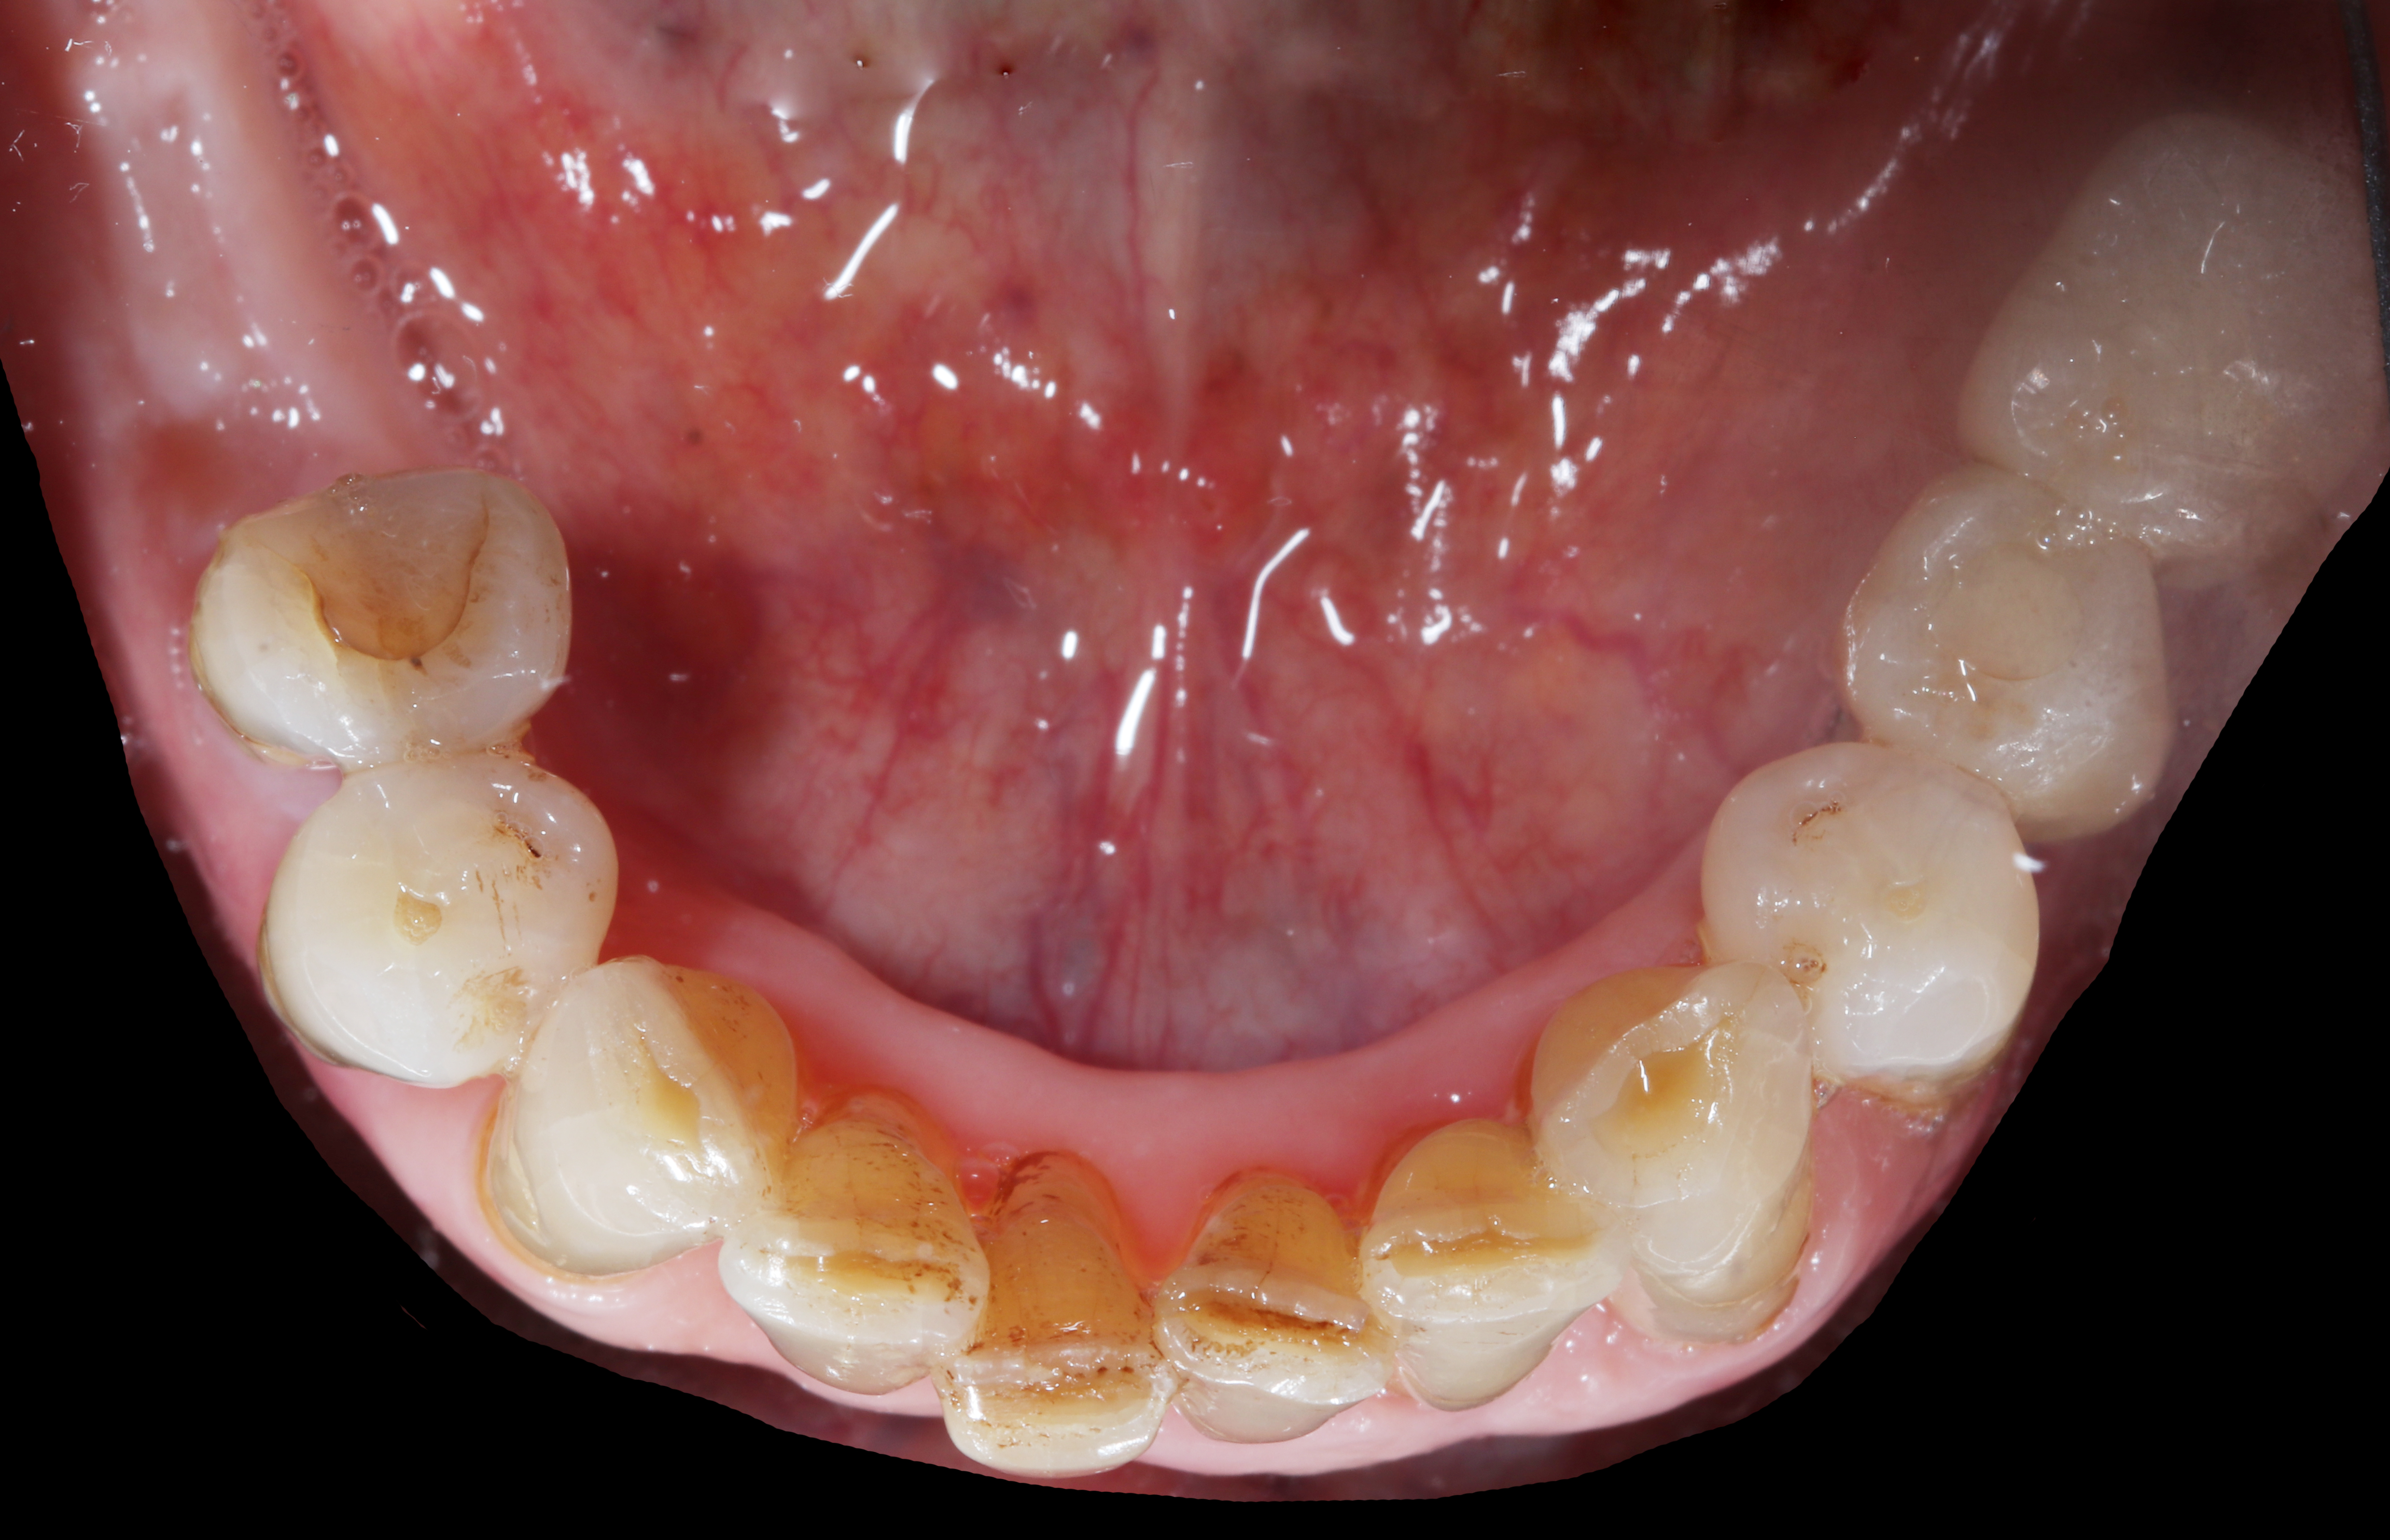

Αρχική κατάσταση - Μασητική άποψη